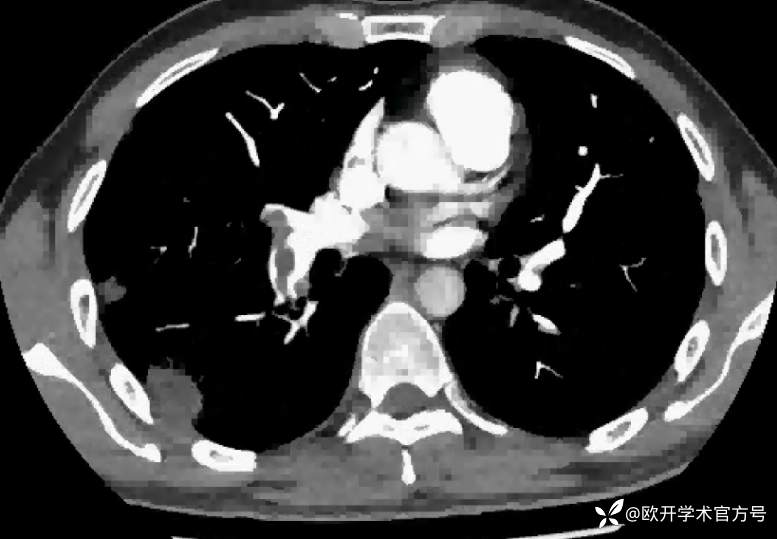

辅助检查:下肢静脉彩超提示:右下肢深静脉血栓形成。肺动脉 CTA 提示:右肺动脉主干可见充盈缺损。

主要诊断: 1.下肢深静脉血栓形成 右下肢 急性期 混合型;2.肺栓塞 中高危组